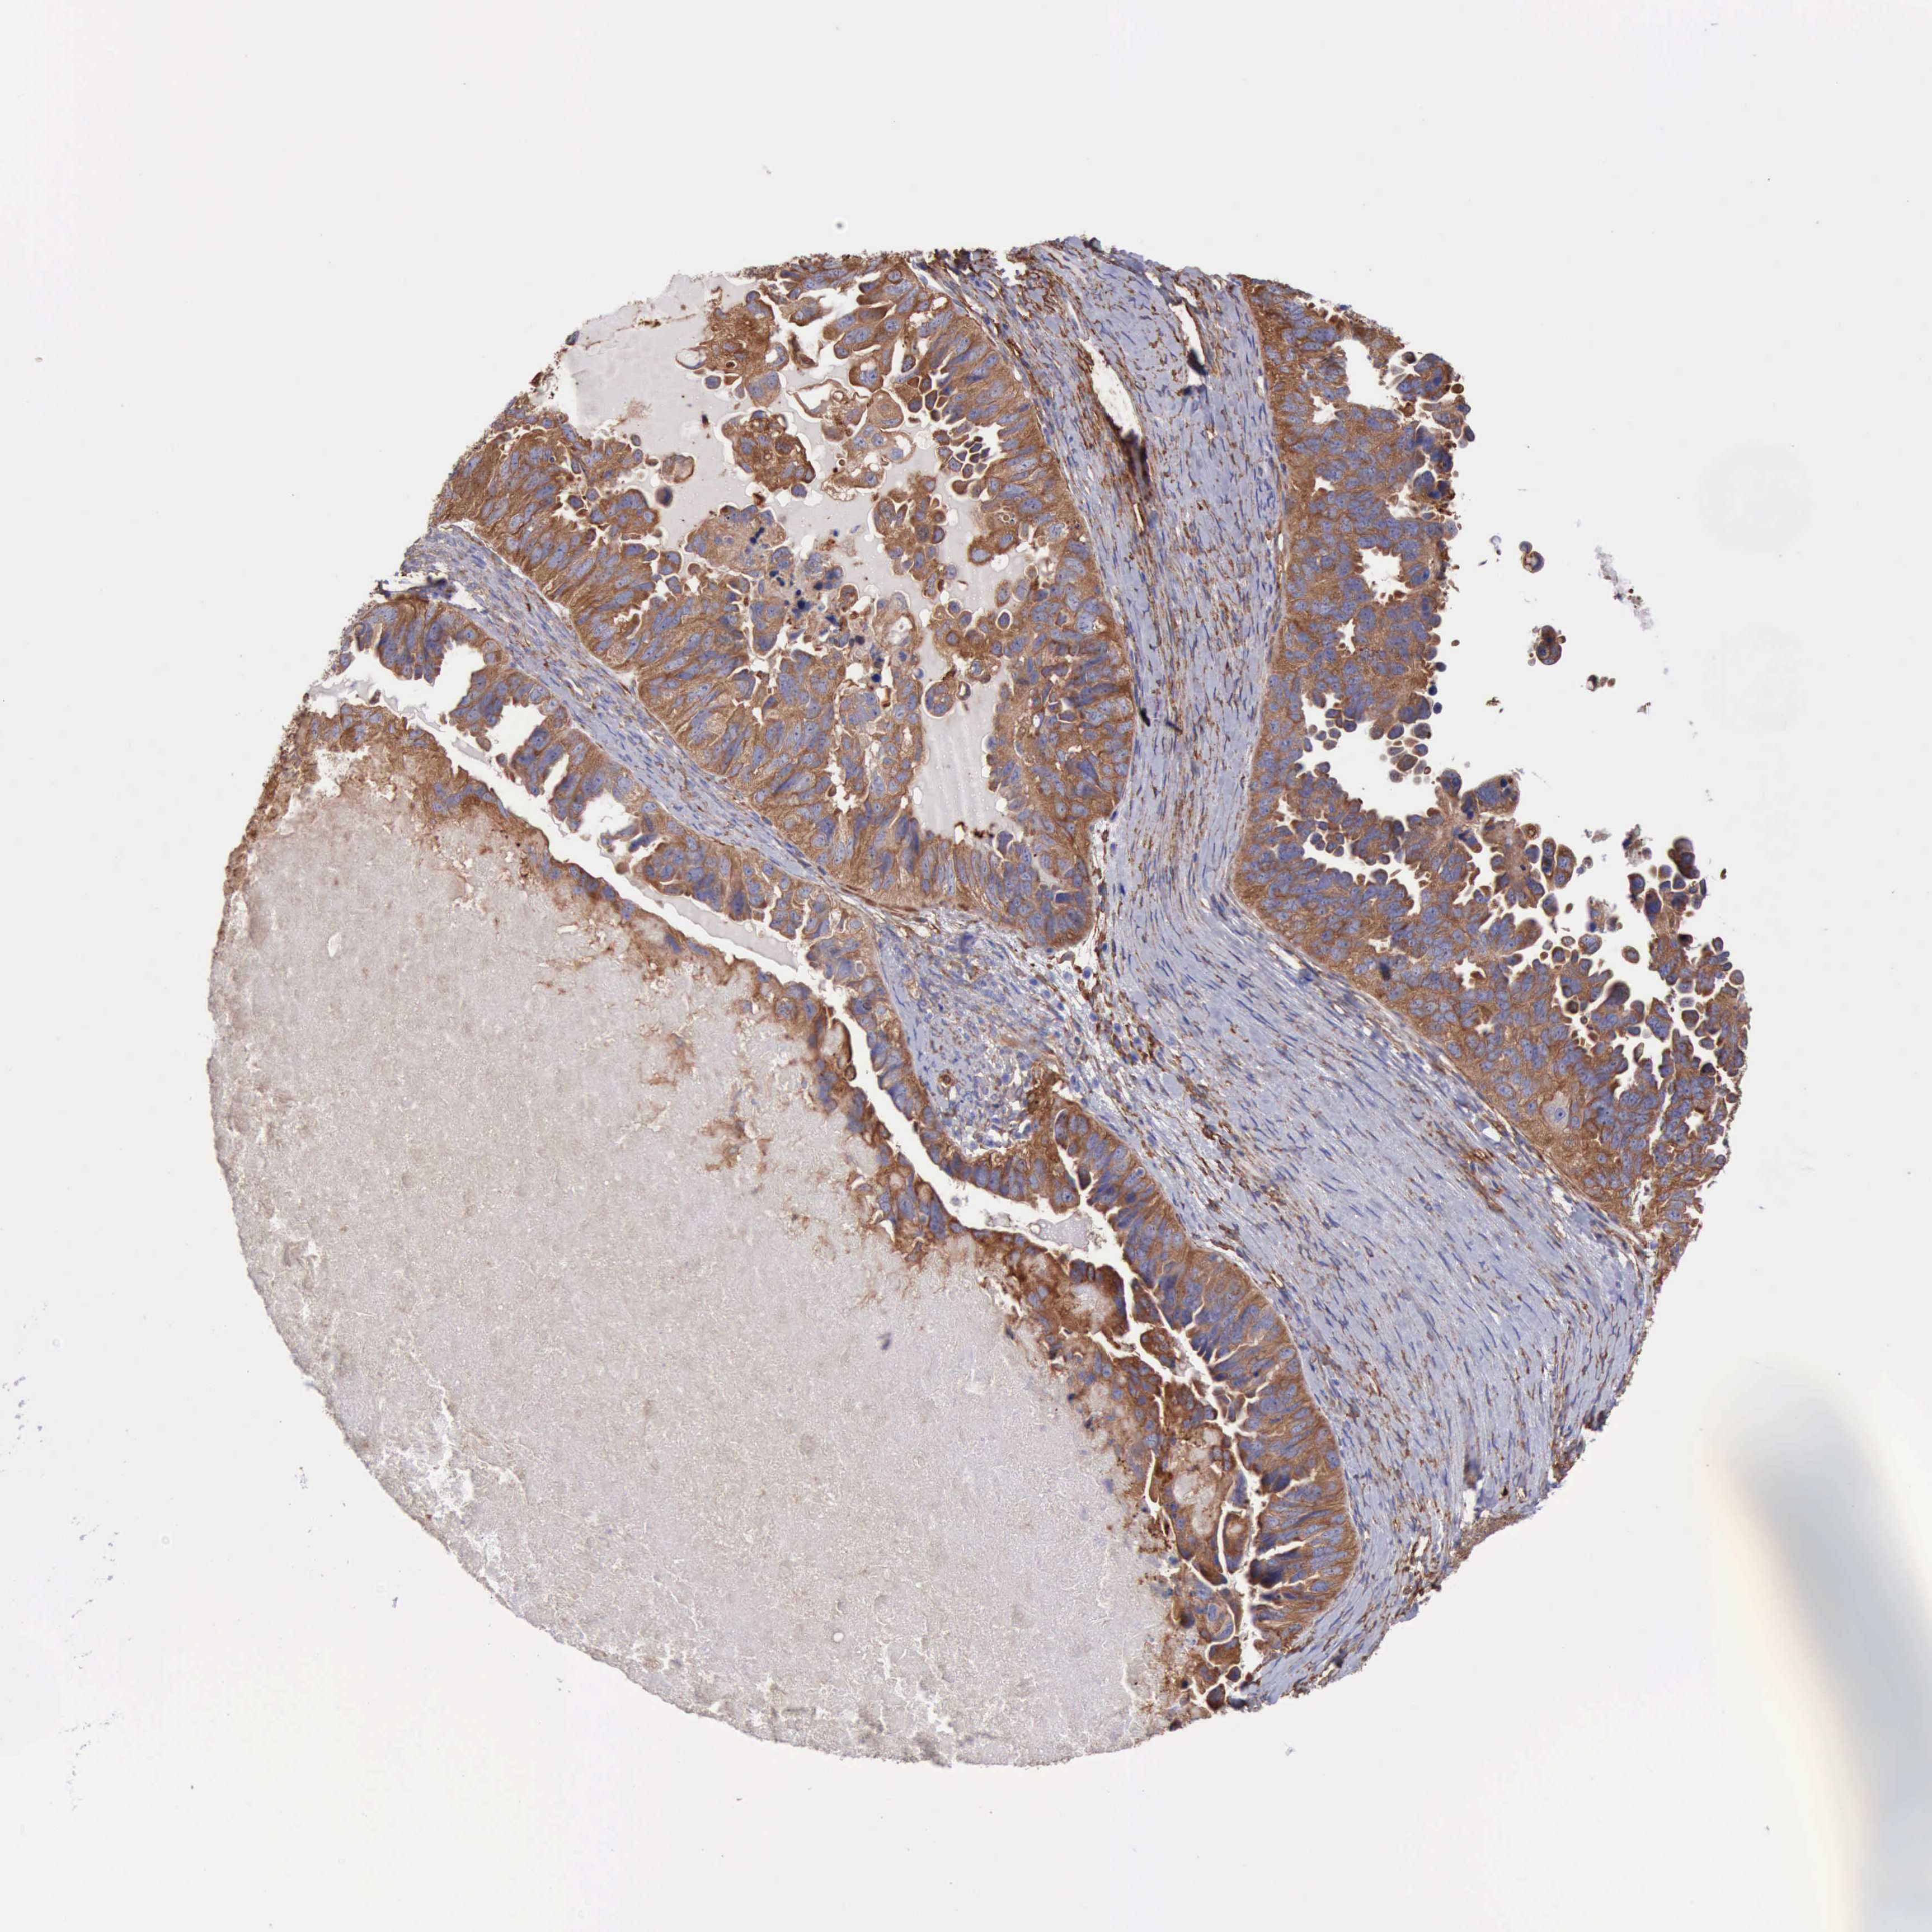

OVARIAN CANCER - Protein expressioni

A mouse-over function shows sample information and annotation data. Click on an image to view it in a full screen mode. Samples can be filtered based on level of antibody staining by selecting one or several of the following categories: high, medium, low and not detected. The assay and annotation is described here.

Note that samples used for immunohistochemistry by the Human Protein Atlas do not correspond to samples in the TCGA dataset.

Antibody stainingi

Antibody staining in the annotated cell types in the current human tissue is reported as not detected, low, medium, or high, based on conventional immunohistochemistry profiling in selected tissues. This score is based on the combination of the staining intensity and fraction of stained cells.

Each image is clickable and will lead to virtual microscopy that enables deeper exploration of all samples and also displays staining intensity scores, fraction scores and subcellular localization as well as patient and tissue information for each sample.

Antibody HPA001115

Antibody HPA002925

Antibody CAB000356

Staining

High

Medium

Low

Not detected

Cystadenocarcinoma, mucinous, NOS

Carcinoma, endometroid

Cystadenocarcinoma, serous, NOS